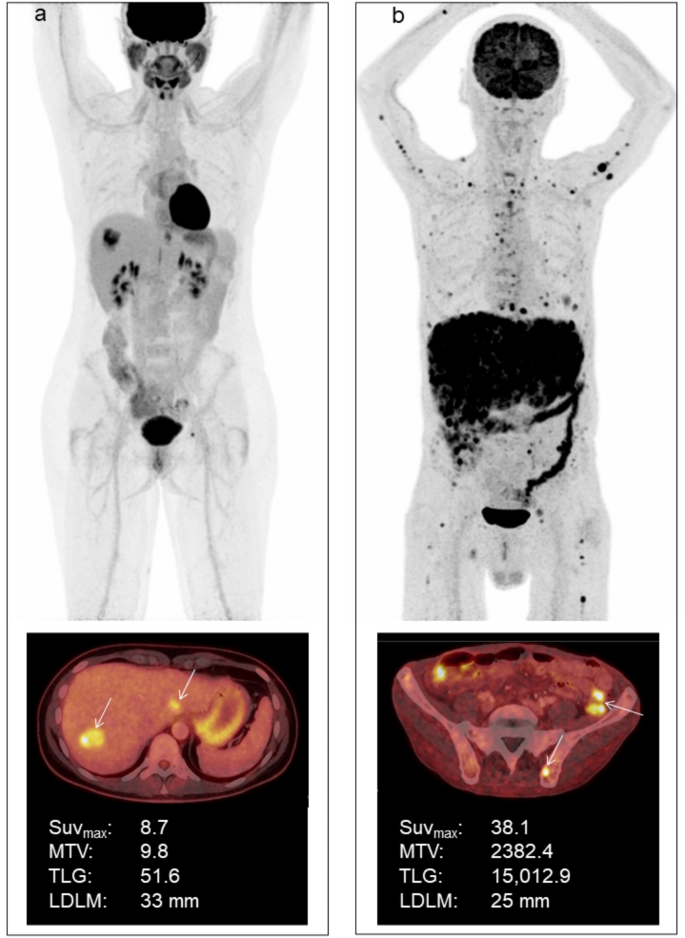

LDLM was measured on an axial image of liver MRI by author and radiologist CWB. If a liver MRI was unavailable or not performed, the LDLM was measured on an axial image of the CT correlate as part of the clinical examination. All clinically described metastatic lesions were outlined using a fixed SUV threshold of 4.0, which made it possible to discriminate tumor tissue from healthy metabolically active liver tissue16. Delineations of all lesions were performed by physician TGH and verified by physician and specialist in nuclear medicine KM. SUVmax, MTV, and TLG for each delineated lesion were measured, and whole-body MTV and TLG were subsequently summed for each patient. In three patients presenting with metastatic disease at primary diagnosis, the metabolic activity of the primary eye tumor was included in the analysis. Among patients with liver metastases, liver-SUVmax, liver-MTV, and liver-TLG for all liver lesions were obtained separately. In 12 cases with 18F-FDG-uptake < SUV 4.00 in the metastatic lesions, SUVmax was determined using the co-registered CT or MRI correlate to identify the metastatic lesions. Images of two representative patients are illustrated in Fig. 4.

(a) Whole-body 18F-FDG PET/CT image of a female patient with two liver metastases from posterior uveal melanoma with an overall survival of 18 months. The two liver metastases are marked with arrows on the axial image; b) Whole-body 18F-FDG PET/CT image of a male patient with posterior uveal melanoma metastasized to various organs, including liver, lung, pleura, bone, muscle, lymph nodes, and the thyroid, and with an overall survival of 1 month. The axial image shows a metastasis in the right iliac bone and two carcinosis elements (arrows).